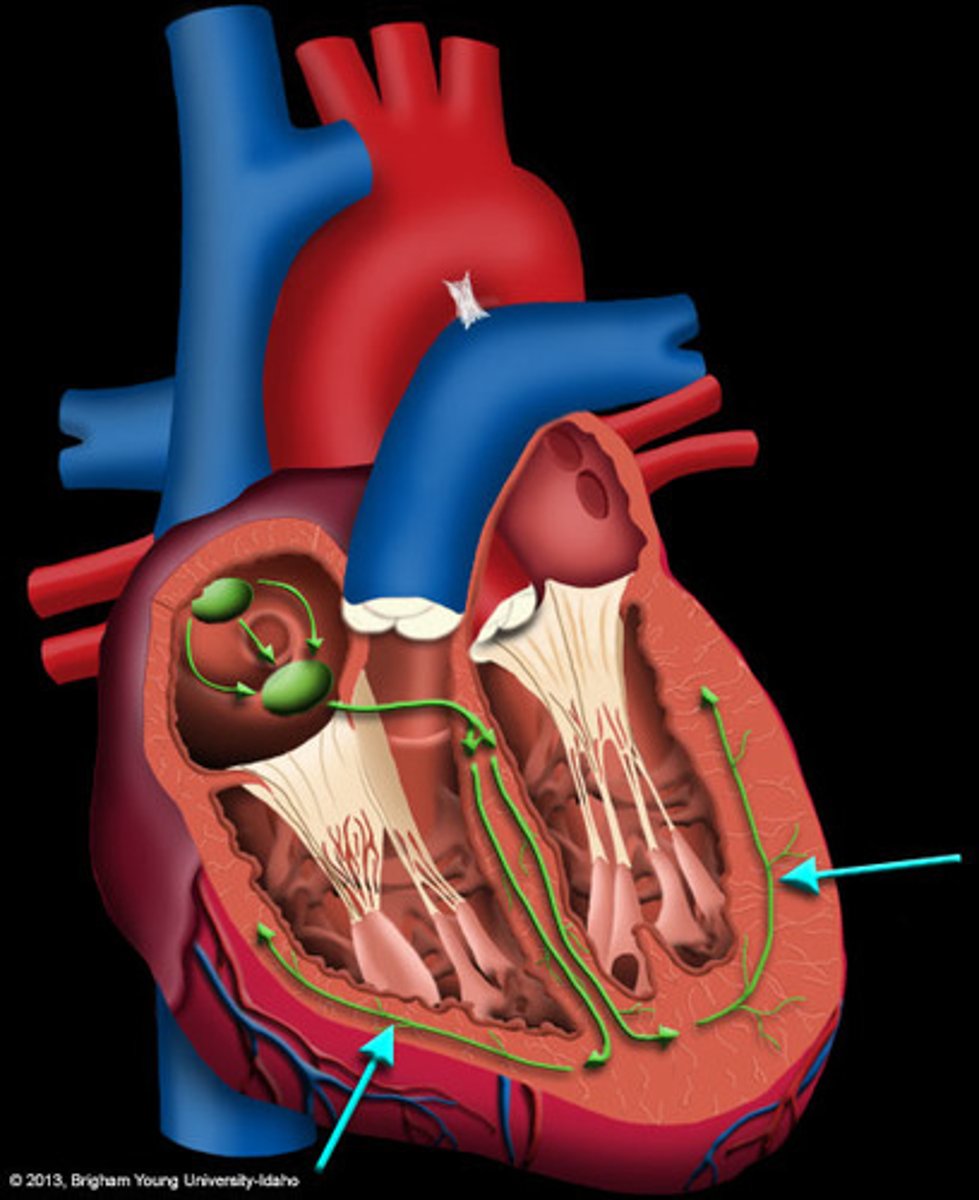

Anatomy of the Heart

2 Types of Chambers in the Heart

- Atrium

- Ventricles

Atrium (2)

A thin-walled reservoir for holding blood, located at the upper chamber of the heart

Ventricle (2)

The thick walled muscular pumping chamber of the heart located at the bottom chamber of the heart

2 Main Types of Valves of the Heart

- Atrioventicular

- Semilunar

Atrioventricular Valves (AV) (2)

The valves that separate the atria and the ventricles

The 2 Atrioventicular Valves of the Heart

- Tricuspid

- Mitral

Tricuspid Valve

- The right AV valve separating the right atrium from the right ventricle

- Connected by 3 chordae tendinae

Mitral (Bicuspid) Valve

- The left AV valve separating the left atrium from the left ventricle

- Connected by 2 chordae tendinae

Chordae Tendinae

Fibers (heart strings) attatched to the tricuspid and mitral valve which pull it closed when papillary muscles contract, preventing back flow of blood

Semilunar Valves (SV) (2)

Valves located between the ventricles and the pulmonary arteries and aorta

The 2 Semilunar Valves of the Heart

- Pulmonic

- Aortic

Pulmonic Valve

The SV valve of the right side of the heart

Aortic Valve

The SV valve of the left side of the heart

The 4 Great Vessels of the Heart

- Superior/inferior venae cavae

- Pulmonary artery

- Pulmonary veins

- Aorta

Superior/Inferior Venae Cavae

The large veins that empty into the right atrium of the heart and return unoxygenated venous blood to the right side of the heart

Pulmonary Artery

Artery carrying oxygen-poor blood from the heart to the lungs

Pulmonary Veins

Veins carrying oxygenated blood from the lungs to the heart

Aorta

The largest artery in the body which carries oxygenated blood from the heart throughout the body

Blood Flow

4 Parts of the Heart's Conduction System

- Sinoatrial (SA) node

- Atrioventricular (AV) node

- Bundle of His

- Purkinje fibers

Sinoatrial (SA) Node

Pacemaker of the heart conduction system, located at the right atrium (light blue)

Atrioventricular (AV) Node

The part that relays electrical impulses from atria into the bundle of his in the heart's conduction system; delayed slightly (yellow)

Bundle of His

Part of the heart's conduction system that transmits the cardiac impulse from the atrioventricular node to the purkinje fibers (red)

Purkinje Fibers

Fibers in the ventricles that transmit impulses to the right and left ventricles, causing them to contract